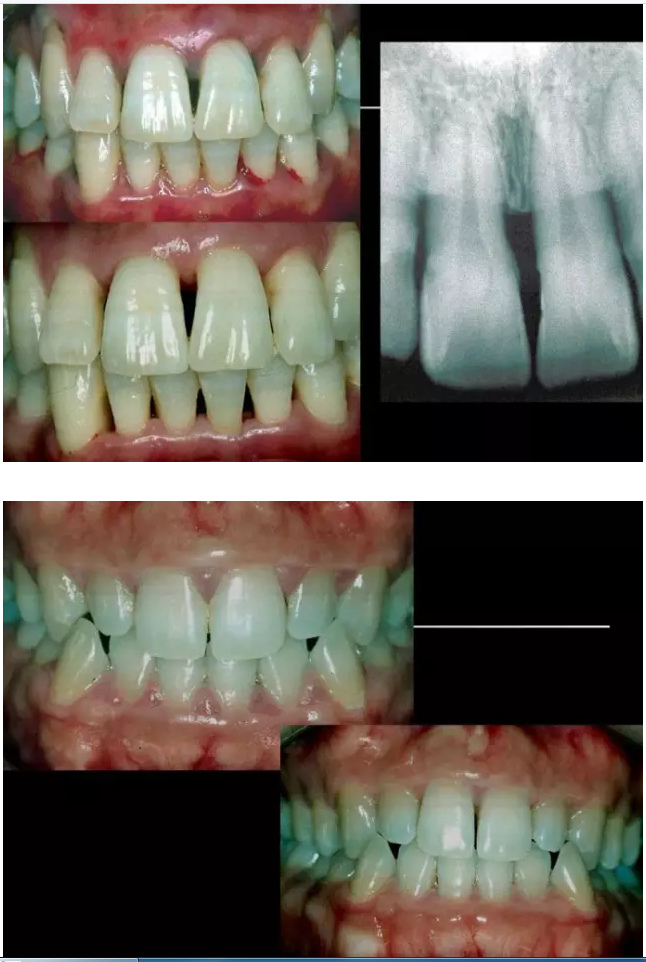

相關(guān)牙周防治